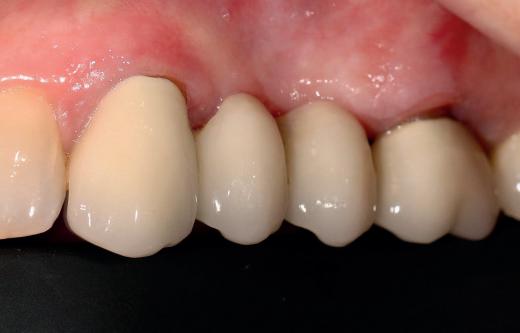

Case 1: Anterior tooth restoration with composite

Case 2: Posterior tooth restoration with composite

Restorations with BEAUTIFIL II LS, BEAUTIFIL Flow Plus X and OneGloss by Erik-Jan Muts, M.Sc., Netherlands